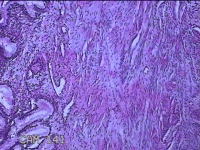

宫颈组织

性别

女

年龄

44岁

临床诊断

宫颈赘生物

一般病史

发现宫颈赘生物2年余。

标本名称

大体所见

灰白暗红色组织3.8x1.5x0.8cm一块,表面光滑,以宫颈12点缝线标记处切开,切面灰白粉红色,质软,宫颈3点处见灰白粉红色囊性肿物1.8x1.5x0.3cm一个,切开肿物,内见大量乳白色内容物,囊壁厚0.1cm。